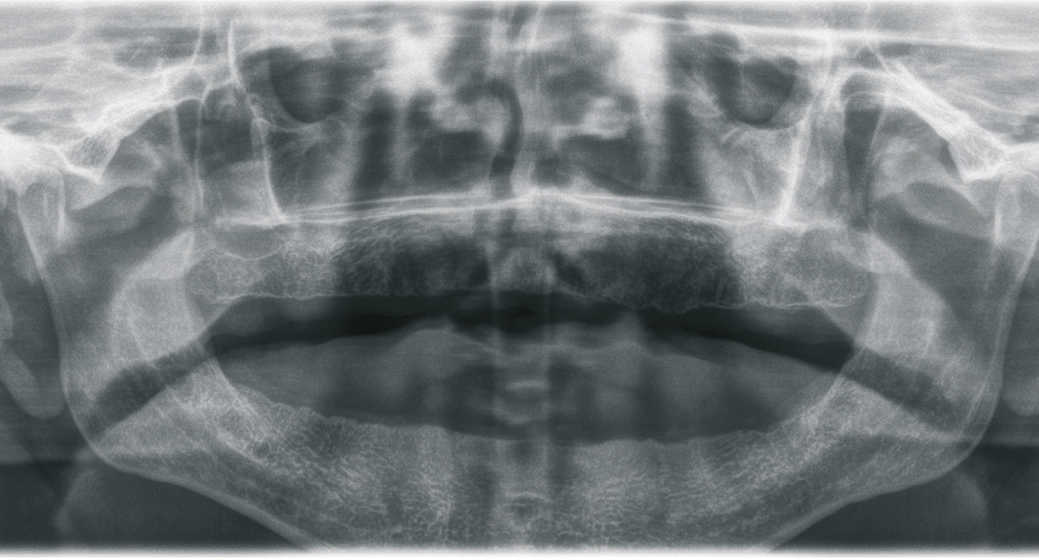

Der 49-jährige Patient trägt im Oberkiefer eine Prothese. Die Prothese im Unterkiefer hat ihn immer gestört, weswegen er diese schon länger nicht mehr getragen hat. Die Abbildungen 1 bis 3 zeigen den Ausgangsbefund. Während der Oberkiefer klinisch noch gut für Implantate geeignet erscheint, können im Unterkiefer schon Zweifel aufkommen. Bei genauerer Betrachtung des Oberkiefers in der Schichtaufnahme (OPG) kommt jedoch die Vermutung auf, dass der Knochen dünn sein könnte. Das war der Grund, warum wir vor der Implantation ein DVT erstellt haben.

Die Abbildungen 1 bis 3 zeigen die Ausgangssituation. Zuerst wurde nach der Herstellung einer Prothese eine Implantatplanung gemacht. In den Abbildungen 5 bis 7 zeigt sich die Herausforderung in diesem Fall: Geringe Platzverhältnisse für die Implantate im Knochen. Nachdem die erstellten Daten verschickt wurden, bekommen wir die Schablonen zurück (Abb. 8).